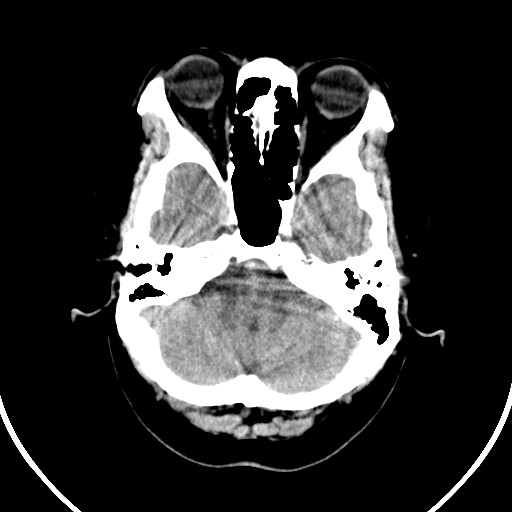

标题: CT21850:女,56岁,右中指淤肿,右手麻痹1天

女,56岁,右中指淤肿,右手麻痹1天

双侧侧脑室额角旁对称性略低密度影,边缘模糊,无占位效应,考虑轻度脑白质稀疏症(病人有高血压吗).,右枕叶低密度影多为伪影,不放心薄扫一下.